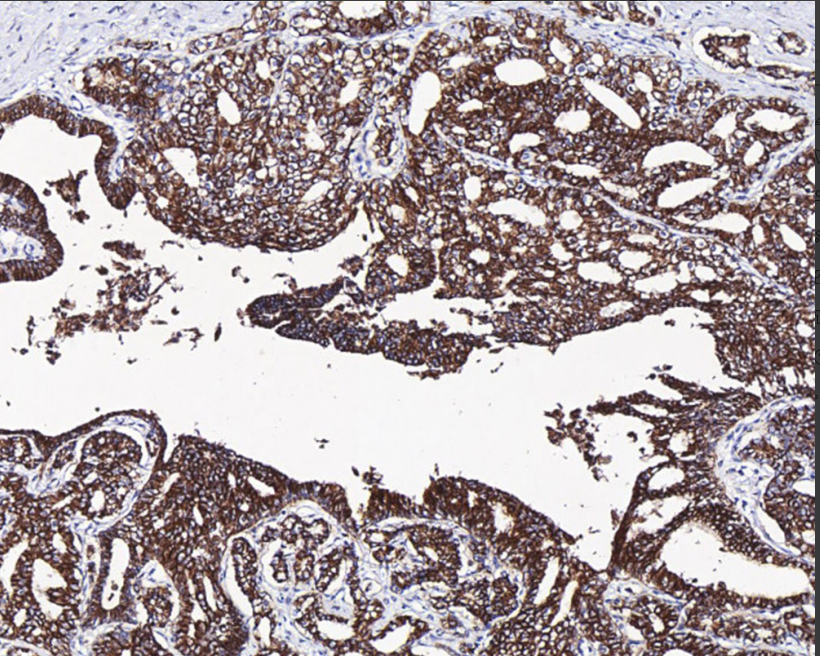

Cellular localization: cytoplasm/membrane

Adaptive tissue: paraffin/frozen

Positive Control: Kidney

Claudin 7 is a member of the Claudin family and is differentially expressed in different types of malignant tumors, including breast, ovarian, hepatocellular, urological, prostate, lung, head and neck, and thyroid cancers, among others.

Claudin 7 antibody reagents can specifically bind to Claudin 7 molecular antigens. Immunohistochemistry kits containing Claudin 7 antibody reagents are suitable for the precise diagnosis of breast cancer, gastric cancer, and colon cancer.